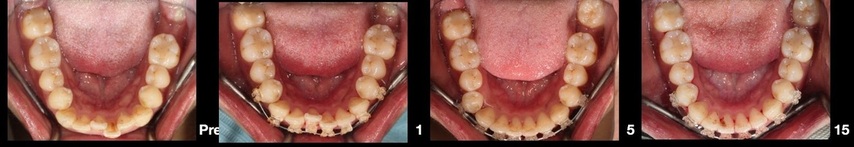

上圖由左至右,為彤彤經過15個月的矯正器治療過程,

原本不整齊的下排牙齒,矯正過後,已經慢慢回到漂亮的排列嚕!